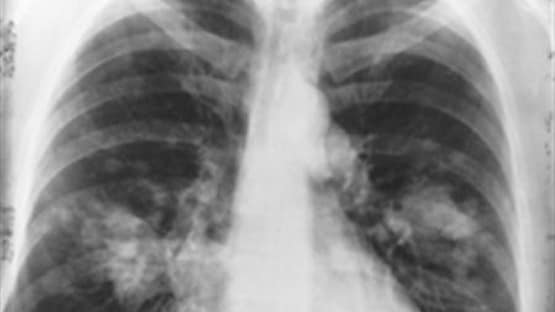

कोरोना वायरस न सिर्फ इंसान के फेफड़ों पर हमला करता है बल्कि किडनी, लीवर, हार्ट, ब्रेन, नर्वस सिस्टम, स्किन और Gastrointestinal Tract को भी नुकसान पहुंचाता है. न्यूयॉर्क के डॉक्टरों ने मरीजों की रिपोर्ट्स की समीक्षा के बाद ये बात कही है. कोरोना वायरस से सबसे बुरी तरह प्रभावित होने वाले शहरों में न्यूयॉर्क शामिल है.

सीएनएन की रिपोर्ट के मुताबिक, डॉक्टरों ने कोरोना मरीजों की रिपोर्ट की समीक्षा के बाद पाया कि यह वायरस इंसान के लगभग हर महत्वपूर्ण अंग को निशाना बनाता है. कोरोना वायरस सीधे मरीजों के अंगों को क्षतिग्रस्त कर देता है और खून जमने लगता है. धड़कन प्रभावित होती है, किडनी से ब्लड आने लगते हैं, स्किन पर रैश दिखते हैं.